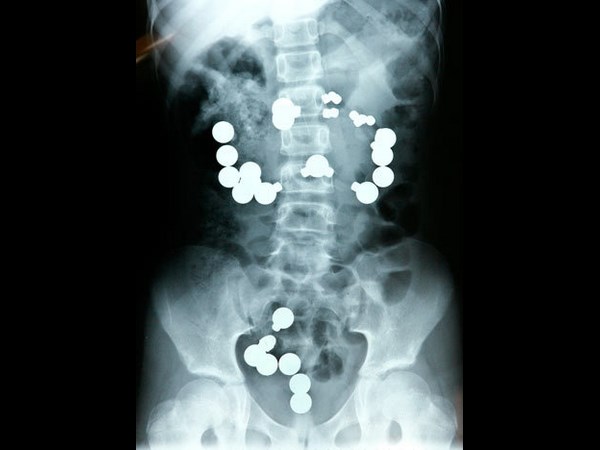

மருத்துவ உலகம் கண்டு வியந்த எக்ஸ் ரே படங்கள்

வயிற்றில் மொபைல் உள்ளது.